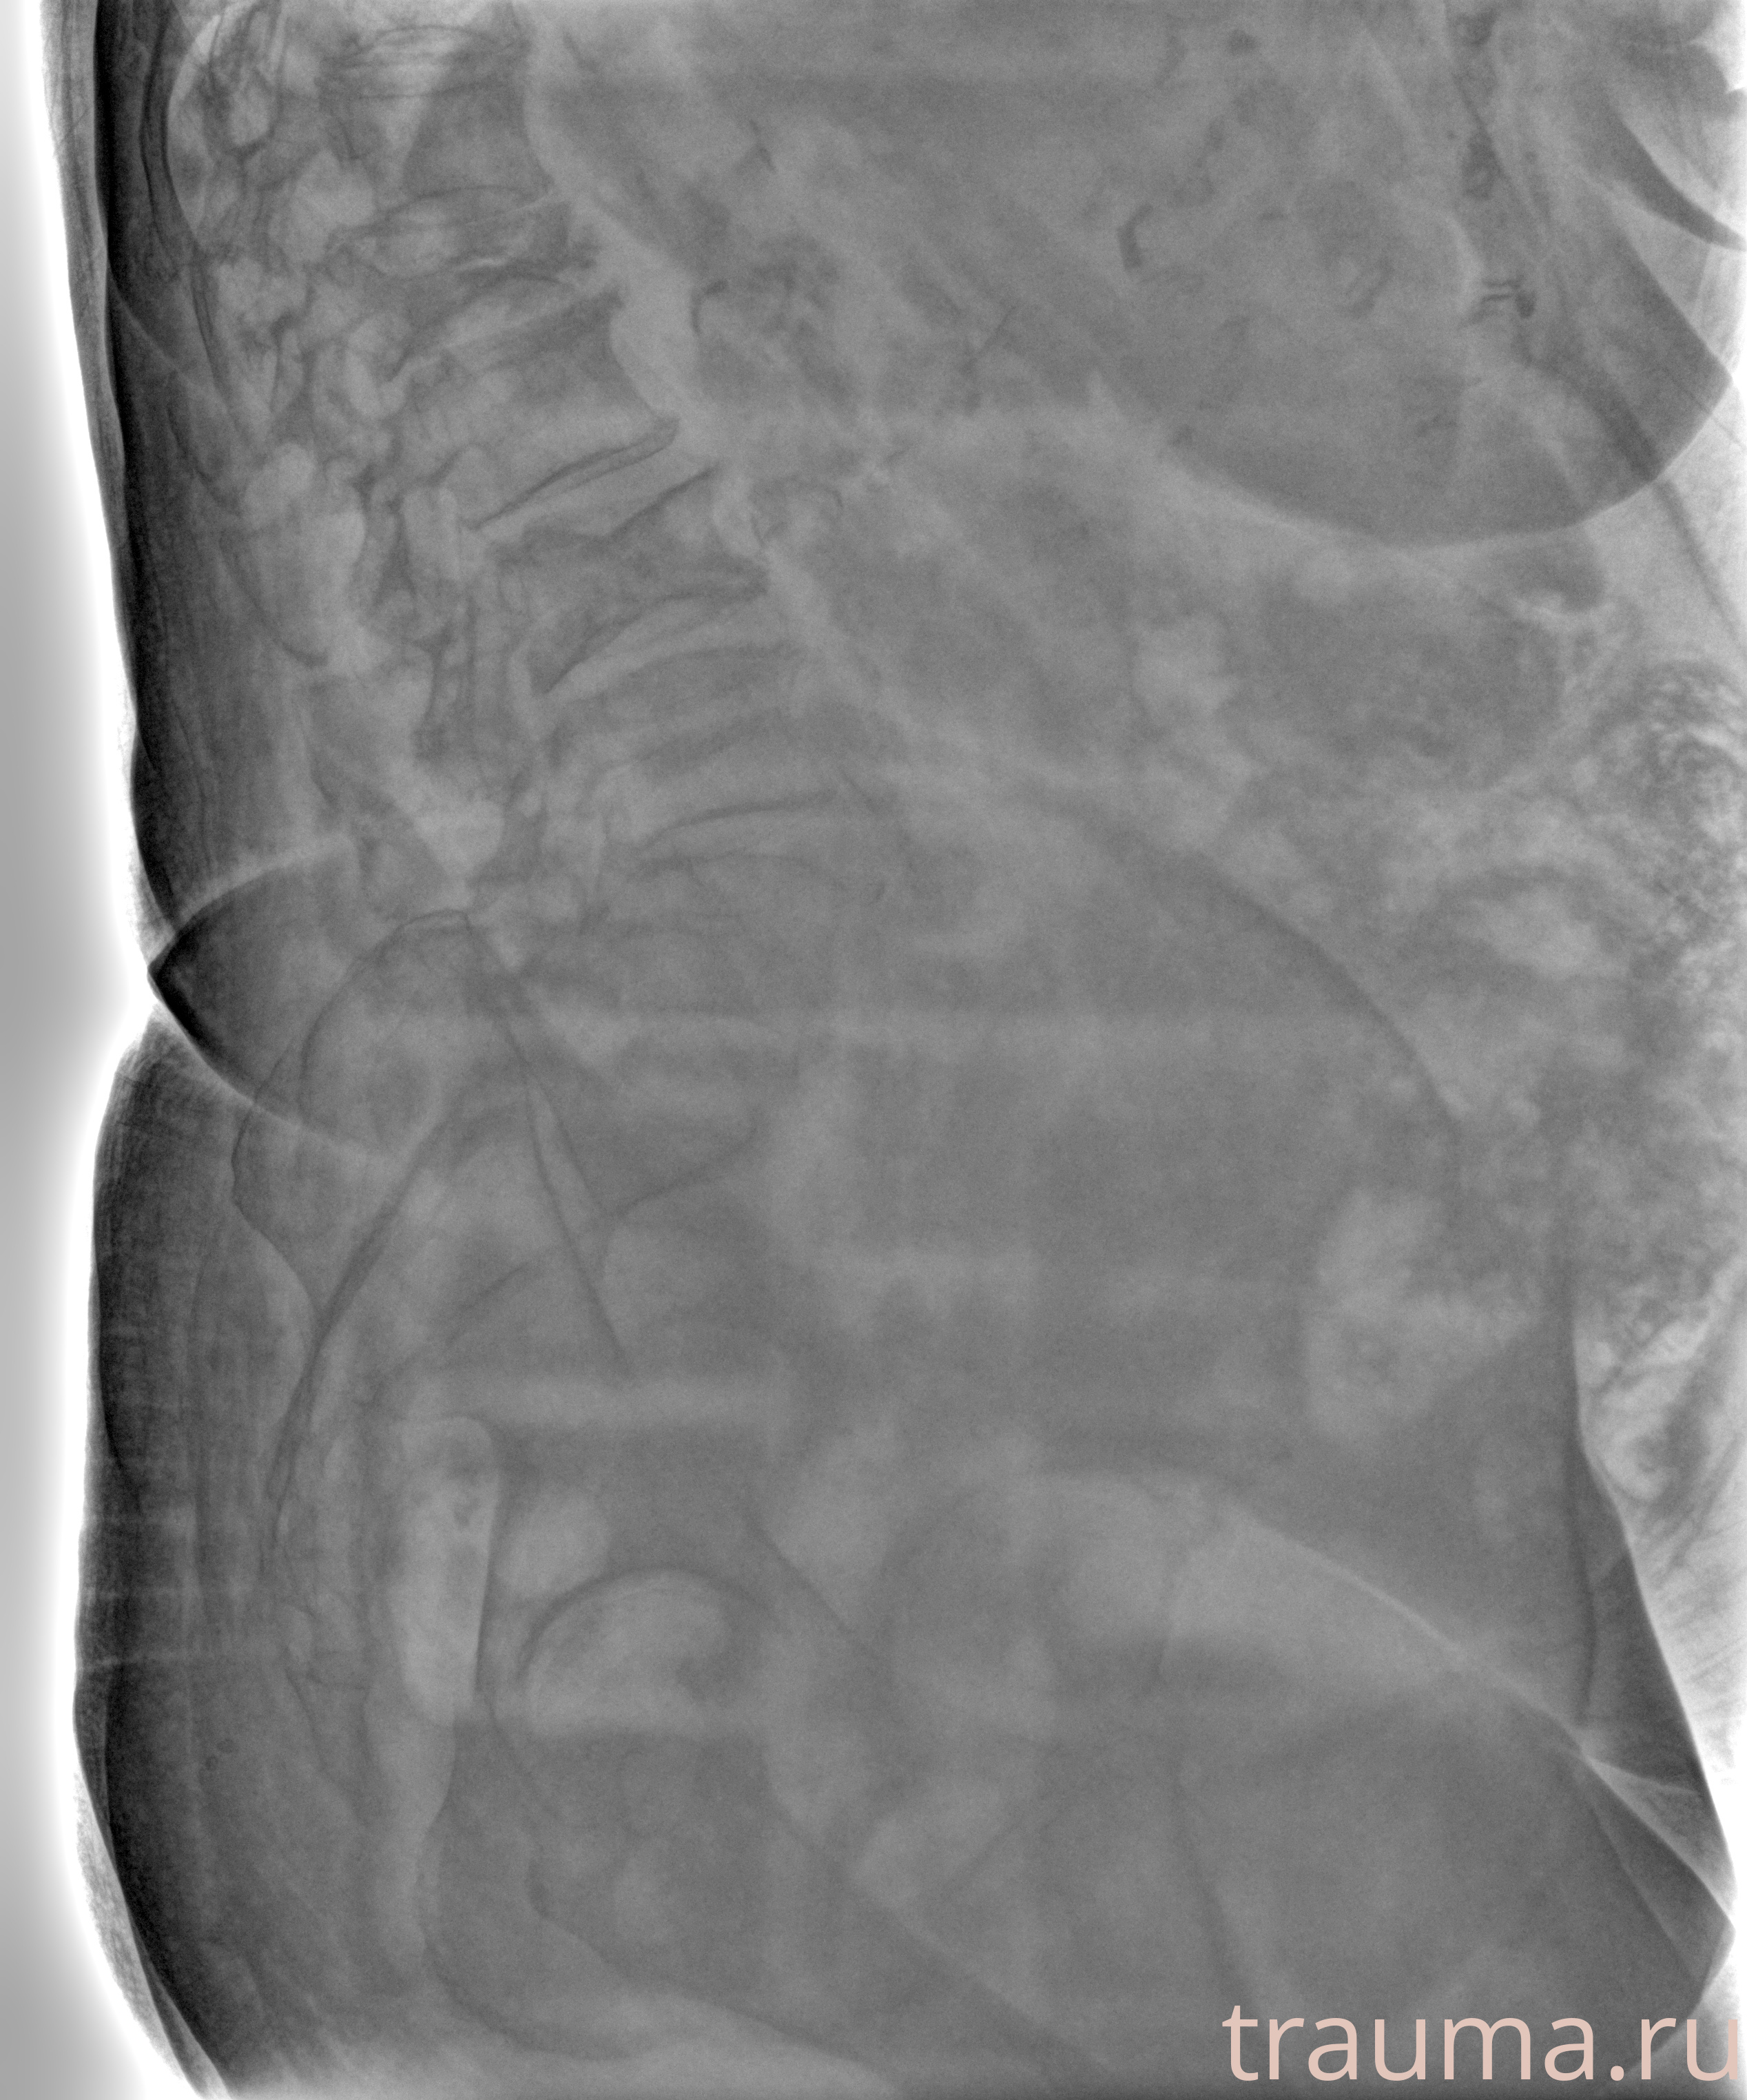

Рентген на дому: по вашему адресу приезжает врач-рентгенолог, травматолог-ортопед с мобильным рентгеновским аппаратом, проводит диагностику травмы или заболевания, делает необходимые рентгенограммы, дает рекомендации по дальнейшему лечению. Получить качественные снимки в домашних условиях возможно благодаря уникальной методике, разработанной МосРентген Центром для института  Склифосовского